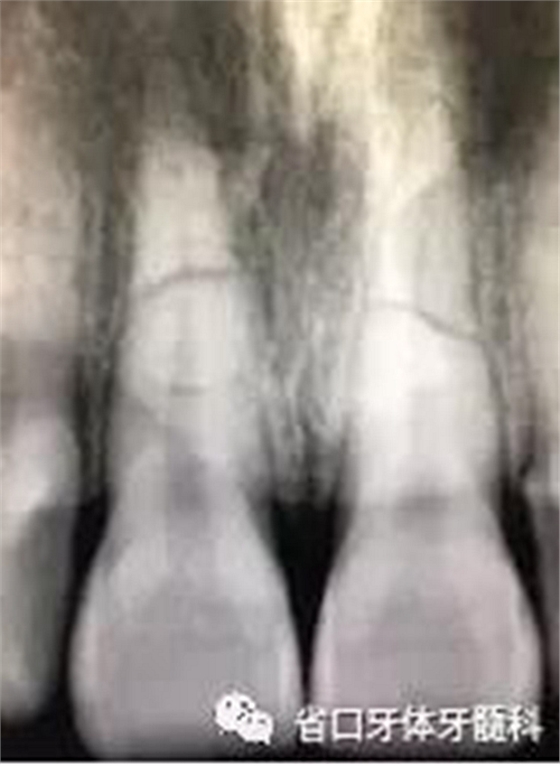

圖1:術(shù)前口內(nèi)照

X線片:11、21根中段見橫行根折線,無移位,根尖無明顯異常。

圖2 術(shù)前根尖片